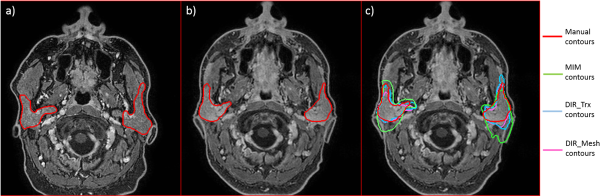

In few cases, contour propagation failed, in particular when MIM was considered; this happened when big deformations and changes in parotid shape occurred (see Figure 5A and B, where a clear difference in head and parotid shape is shown). In this case, MIM had a greater difficulty in recovering parotid contours (green line in Figure 5C), with respect to the other 2 methods (light blue and purple line in Figure 5C).

Figure 5

Example of a failed contour propagation, especially for MIM (green line). A, Magnetic resonance imaging (MRI) acquired before radiation therapy (RT) with manual parotid contours. B, Magnetic resonance imaging acquired after RT with manual parotid contours. C, Magnetic resonance imaging acquired after RT with manual and deformed contours.